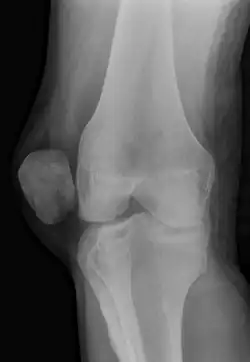

| X-ray showing a patellar dislocation, with the patella out to the side. | |

A patellar dislocation is a knee injury in which the patella (kneecap) slips out of its normal position.[5] Often the knee is partly bent, painful and swollen.[1][2] The patella is also often felt and seen out of place.[1] Complications may include a patella fracture or arthritis.[3]

A patellar dislocation typically occurs when the knee is straight and the lower leg is bent outwards when twisting.[1][2] Occasionally, it occurs when the knee is bent and the patella is struck directly.[1] Commonly associated sports include soccer, gymnastics, and ice hockey.[2] Dislocations nearly always occur away from the midline.[2] Diagnosis is typically based on symptoms and supported by X-rays.[2]